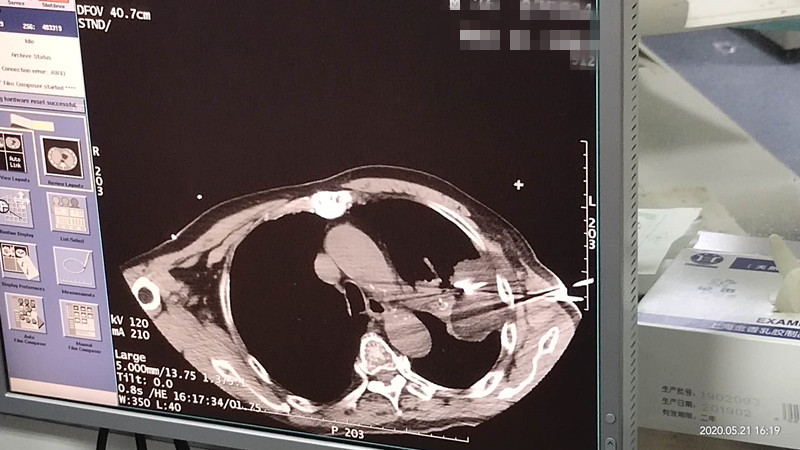

76岁肺部氩氦刀冷冻消融

发布人:美国氩氦刀技术官方网站    发布时间:2020/5/22 15:12:45